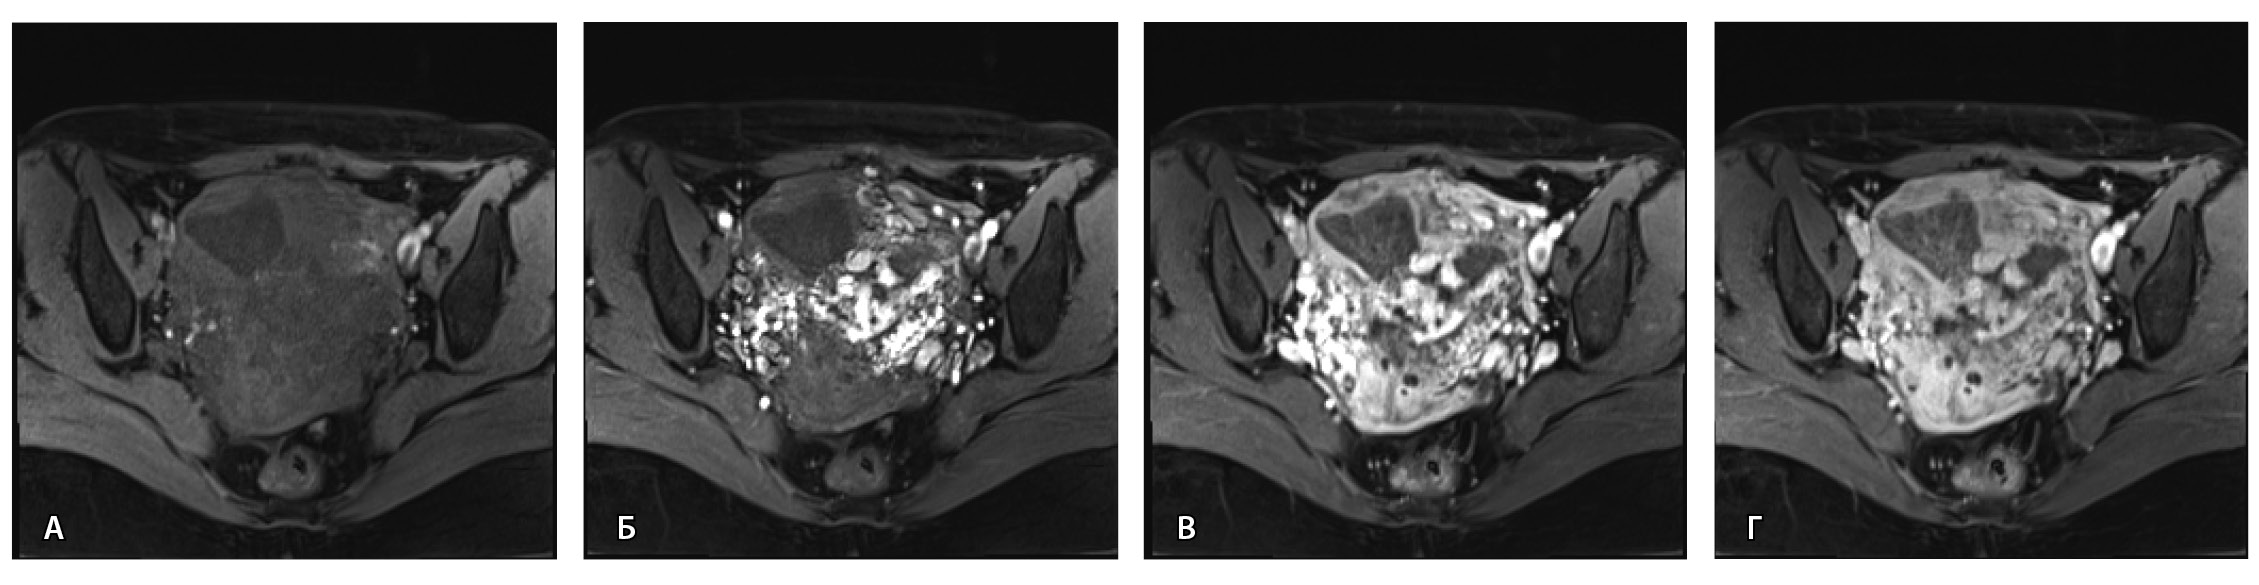

Пациентке выполнено МРТ-исследование на МР-томографе Siemens MAGNETOM Verio с индукцией магнитного поля 3T, с использованием стандартных катушек, в режимах Т1-взвешенного изображения (ВИ), Т2-ВИ, Т2-FS, FIESTA, DWI с получением изображений в сагиттальной, корональной и аксиальной плоскостях, динамическое внутривенное контрастирование (гадопентетовая кислота 0,2 мл/кг массы тела). Матка увеличена в размерах, с признаками снижения зональной дифференциации стенок, усиленным сосудистым компонентом, полость матки расширена с наличием примеси геморрагического содержимого, неравномерным утолщением эндометрия и пристеночными компонентами слизистой. В нижнем маточном сегменте определяется несостоятельный рубец от кесарева сечения, с наличием участка резко истонченной пролабирующей стенки матки слева и наличием дополнительного образования неоднородного сигнала, суммарно до 4,0 × 2,3 × 3,2 см, представленного фрагментами мягкотканного хориона (изоинтенсивного на Т2-ВИ), достигающего серозного покрова матки, и патологического сосудистого компонента в виде расширенных полнокровных сосудов, зон неоангиогенеза (рис. 1). На DWI признаков ограничения диффузии не определялось.

Рис. 1. Остатки вросшего хориона в несостоятельный рубец от кесарева сечения. Магнитно-резонансная томограмма, Т2-взвешенное изображение в сагиттальной (А), корональной (Б), аксиальной (В) плоскостях. Признаки наличия в проекции несостоятельного рубца от кесарева сечения фрагментов ткани вросшего хориона изоинтенсивного сигнала (отмечен звездочкой), с распространением до серозного покрова матки. Стрелками указаны гипоинтенсивные сосуды, зоны неоангиогенеза, артериовенозные сосудистые коллатерали

По наружной поверхности нижнего маточного сегмента и в параметрии определяется наличие полнокровной сосудистой сети с артериовенозными анастомозами. При контрастировании визуализируются фрагментарные участки гиперваскулярного накопления контраста вышеописанным образованием в рубцовой нише, а также определяется наличие артериовенозной сосудистой мальформации (рис. 2).

Рис. 2. Магнитно-резонансная томограмма, динамическое контрастное усиление в режиме Т1-взвешенного изображения FS. До контраста (А), в раннюю артериальную фазу (Б), паренхиматозную фазу (В), выделительную фазу (Г) определяются многочисленные патологические сосуды, зоны неоангиогенеза, сосудистые шунты как в стенке матки, так и в параметрии по типу артериовенозной мальформации